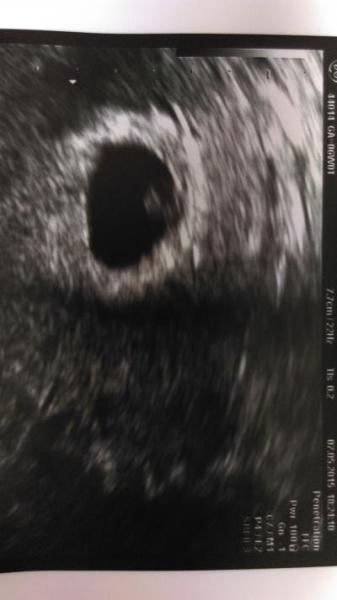

Hatte heute nochmal ein Kontrolltermin, ob das Wachstum diesmal stimmt. Und was soll ich sagen.... Es ist alles super. Alles genau so wie es sein soll. Sogar das Herz hab ich fleißig schlagen sehen Den nächsten Termin hab ich dann erst wieder in 3 Wochen am 29.05. Der Et wurde auf den 31.12. gesetzt. Aber ich bleibe trotzdem einfach hier LG Saskia

Bild zu Zurück vom FA! - Forum für Januar - Mamis

Bin heute 6+0. Ganz frisch in der 7 Ssw . Laut Ultraschallmessung 6+1